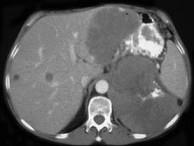

问题 女,38岁,低热乏力并消瘦2月余,CT如图所示,下列说法正确的是()

选项 A.左侧肾上腺区巨大的占位性病灶考虑为肾上腺癌 B.左侧肾上腺区巨大的占位性病灶考虑为嗜铬细胞瘤 C.左侧肾上腺区巨大的占位性病灶考虑为肾上腺腺瘤 D.肺内多发小结节病灶,考虑为肺转移瘤 E.肺内多发小结节病灶,考虑为肺结核

答案 AD